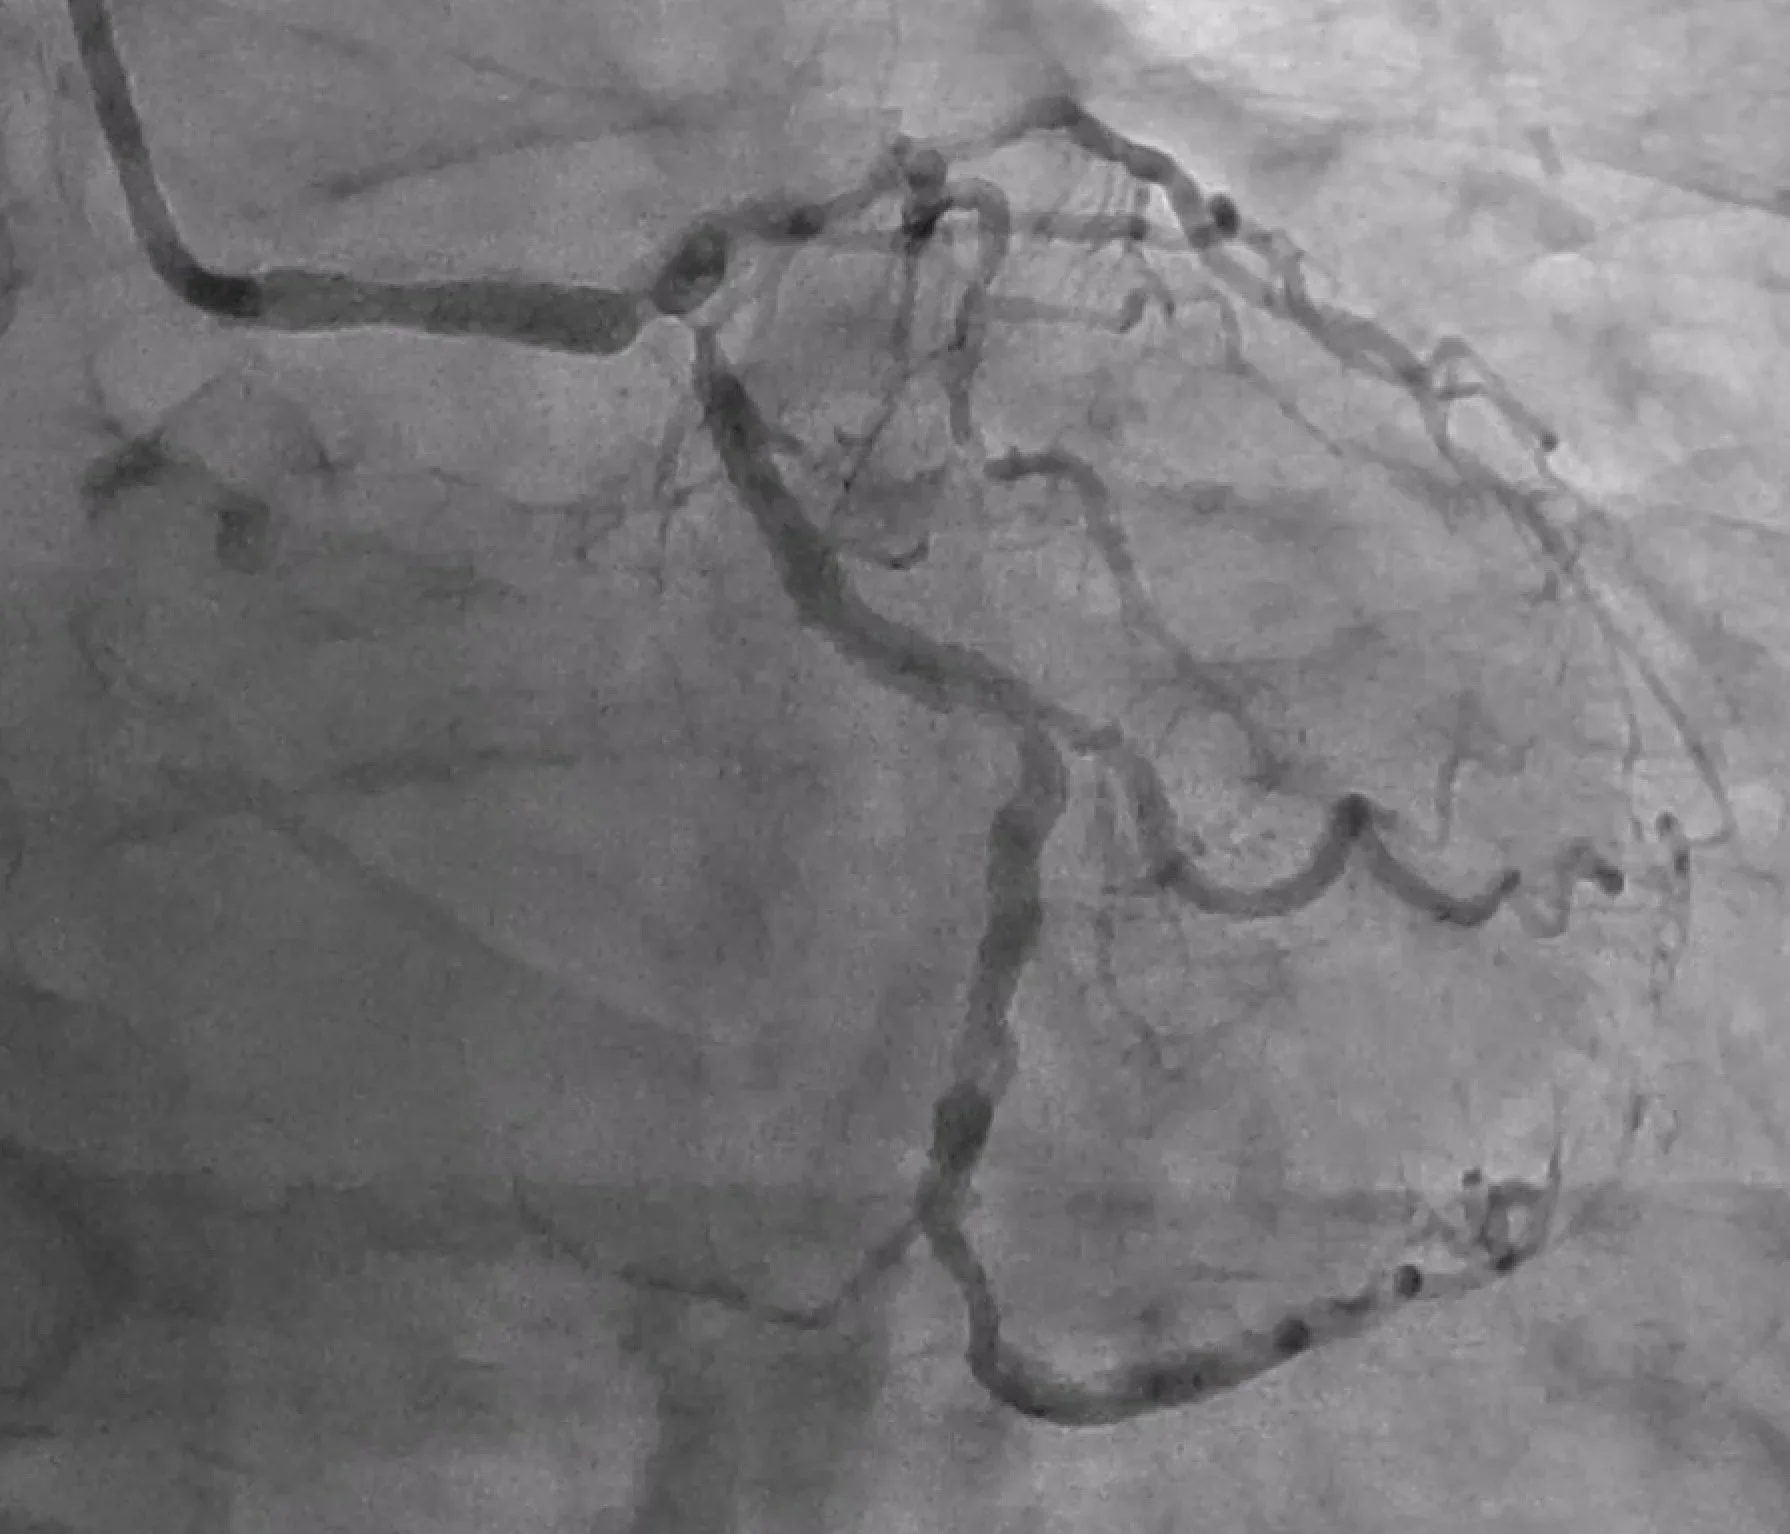

Coronary artery disease (also called coronary heart disease) occurs when fatty plaque builds up in the arteries that supply blood to the heart muscle. Over time, this can narrow the arteries and reduce blood flow—particularly during exertion—causing symptoms such as angina. A sudden plaque rupture with clot formation can lead to a heart attack (myocardial infarction).

• Coronary angioplasty and stenting (PCI)